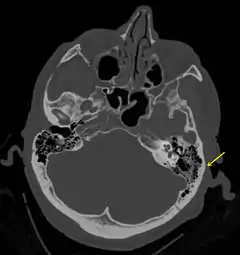

La base del cráneo está formada por el hueso etmoides, el esfenoides, las 2 porciones del hueso frontal, los 2 huesos temporales incluyendo su porción petrosa o peñasco y el hueso occipital. El conjunto se divide en tres compartimentos, la fosa craneal anterior, la fosa craneal media y la posterior. La fractura puede afectar a las tres fosas craneales, pero se localiza preferentemente en determinadas zonas que son puntos débiles de la estructura, entre ellos el techo de la órbita, la lámina cribosa del etmoides y el peñasco del hueso temporal.

![]() Fractura del hueso temporal. | ||